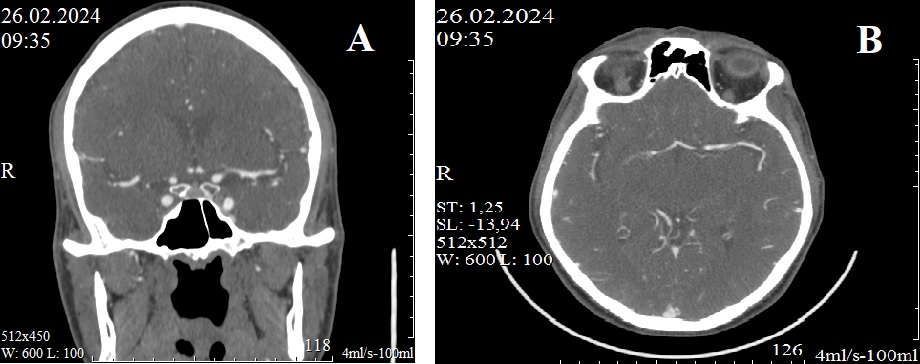

Рисунок 1 - При контрольном исследовании через 21 день кровоток в М1 сегменте левой средней мозговой артерии не нарушен (А, В)